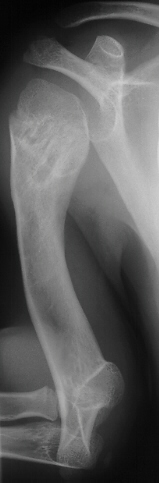

deformity of the metaphyseal region. By age 11 the child had a

good gait pattern however the upper extremity length discrepancy

was becoming a cosmetic and functional concern. X-rays at age

11 show significant angulation developed in the humerus(image

3,4 & 5). However tibial growth was good.